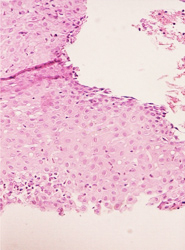

El resultado de una valoración colposcópica de paciente con lesión displásica siempre será confirmado por el estudio histopatológico que realiza el médico anatomopatólogo (estudio de la biopsia tomada en la colposcopía) . A continuación presentamos imágenes histológicas con sus diagnósticos.

• Lesion de alto grado, con anisocitosis y anisocariosis severas, perdida de la cohesividad y orientacion celular.